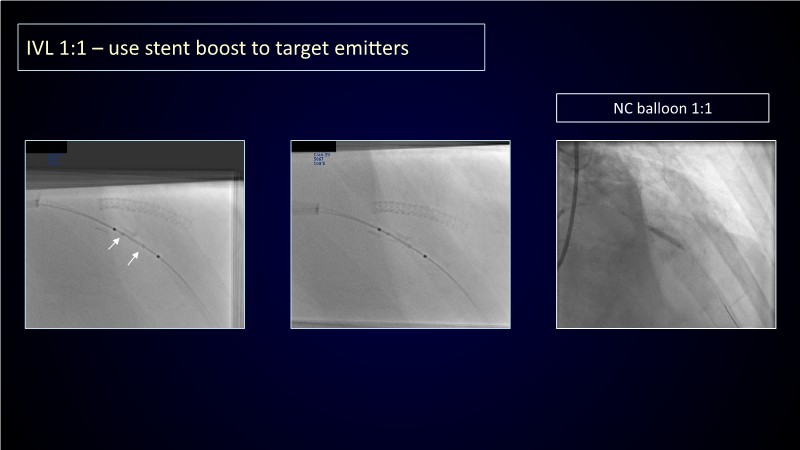

Calcified coronary lesions are a major challenge in PCI. This PCRGulf-GIM 2025 session showcases a complex case with intravascular imaging, highlighting how IVUS 123 guides each step.

From planning the procedure and understanding calcium distribution, to lesion preparation with modern modification tools, and post-PCI assessment to confirm stent expansion and detect complications, this session demonstrates practical, imaging-driven strategies.

Learn how careful preparation and modern techniques improve outcomes in treating severe calcium, calcified nodules, and in-stent restenosis.